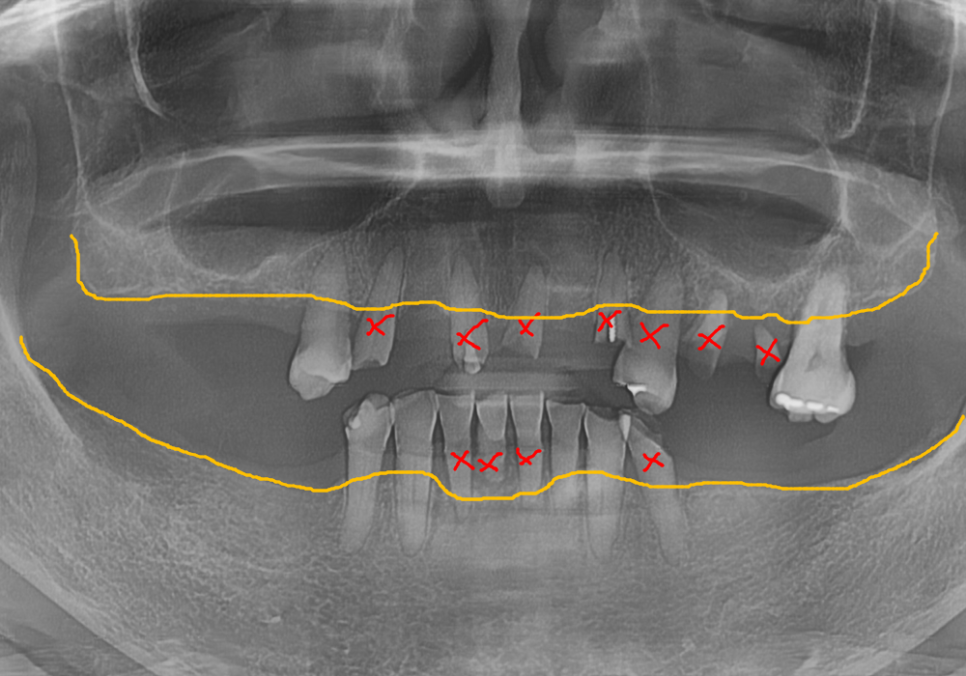

파노라마와 CT를 통해 살펴보니

뿌리 끝에 염증이 가득 잡혀 있었죠.

가장 튼튼해서 살려 쓸 수 있는

위쪽 치아 2개(#14, 27)만 남기고

나머지는 안타깝게도 발치를 결정했습니다.

아래쪽 앞니들은 잇몸뼈가 많이 녹아 흔들리고 있어

총 4개의 치아를 발치하기로 했습니다.